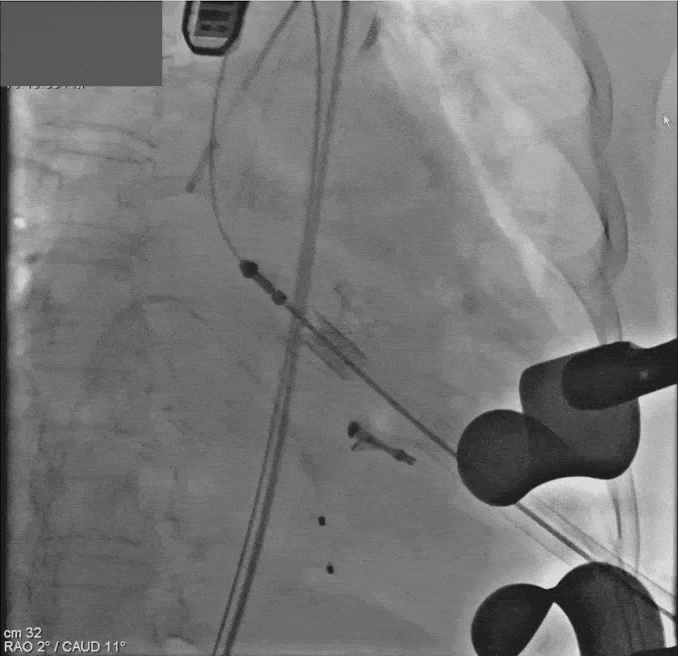

手术于全麻下进行,采用经心尖途径,在超声引导下首先将ValveClamp二尖瓣夹合器顺利植入,夹合器位置稳定,二尖瓣反流基本消失,多切面证实夹合组织充分,双孔化形成,移除器械输送系统。随后通过支撑导丝送入23mm J-Valve介入主动脉瓣,准确入主动脉窦后完全释放瓣膜,撤出输送器。造影评估结果,主动脉瓣反流消失,冠脉开口通畅,无传导阻滞,手术圆满成功。